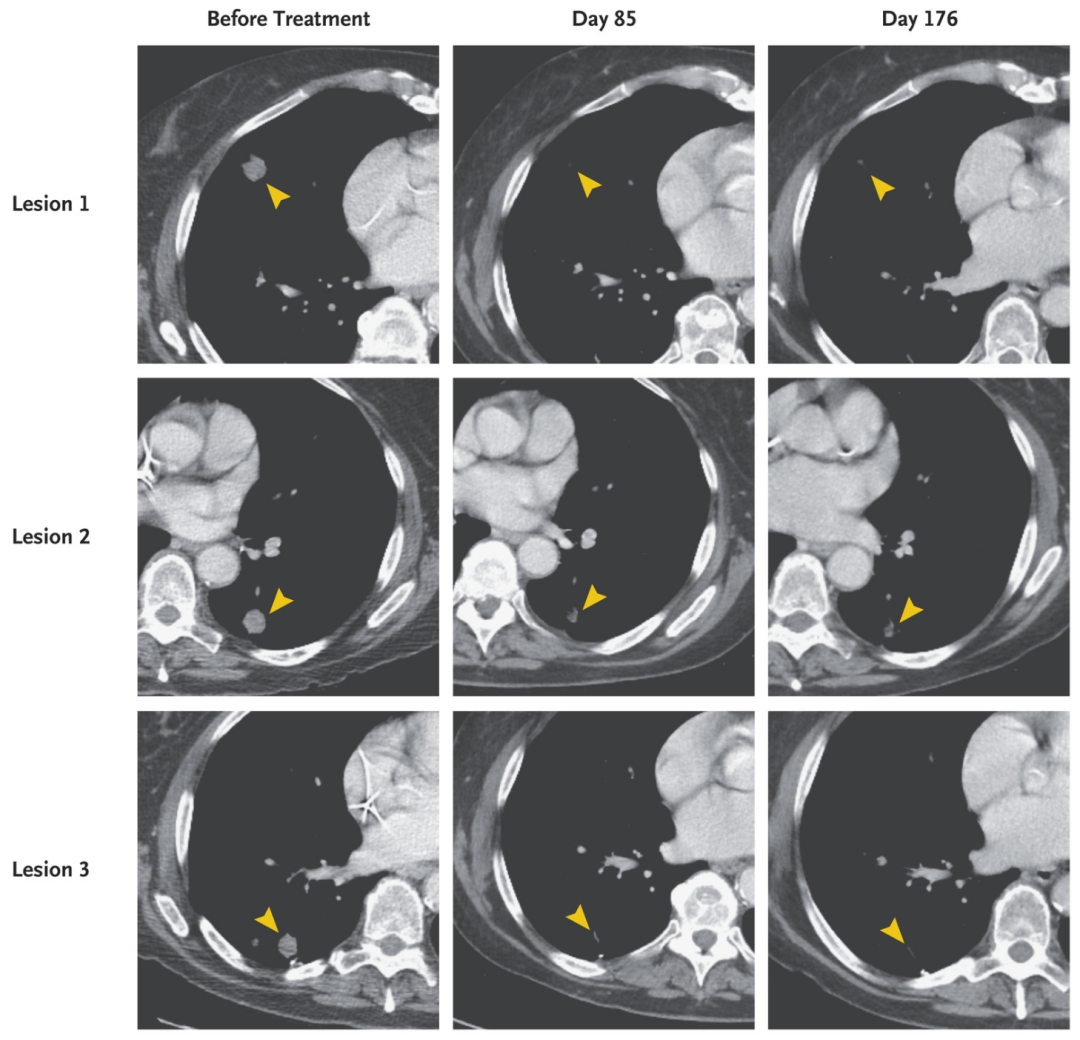

图1 该患者肺部病变的放射学评估

▲图源J Hematol Oncol,版权归原作者所有,如无意中侵犯了知识产权,请联系我们删除

注:红色箭头表示目标病变;★表示原发病变。

图2 该患者胸部计算机断层扫描

▲图源N Engl J Med,版权归原作者所有,如无意中侵犯了知识产权,请联系我们删除

注:本图显示了该患者在回输TCR-T细胞前、输注后85天和176天时,胸部对比增强计算机断层扫描结果,箭头突出显示治疗前后的病变。